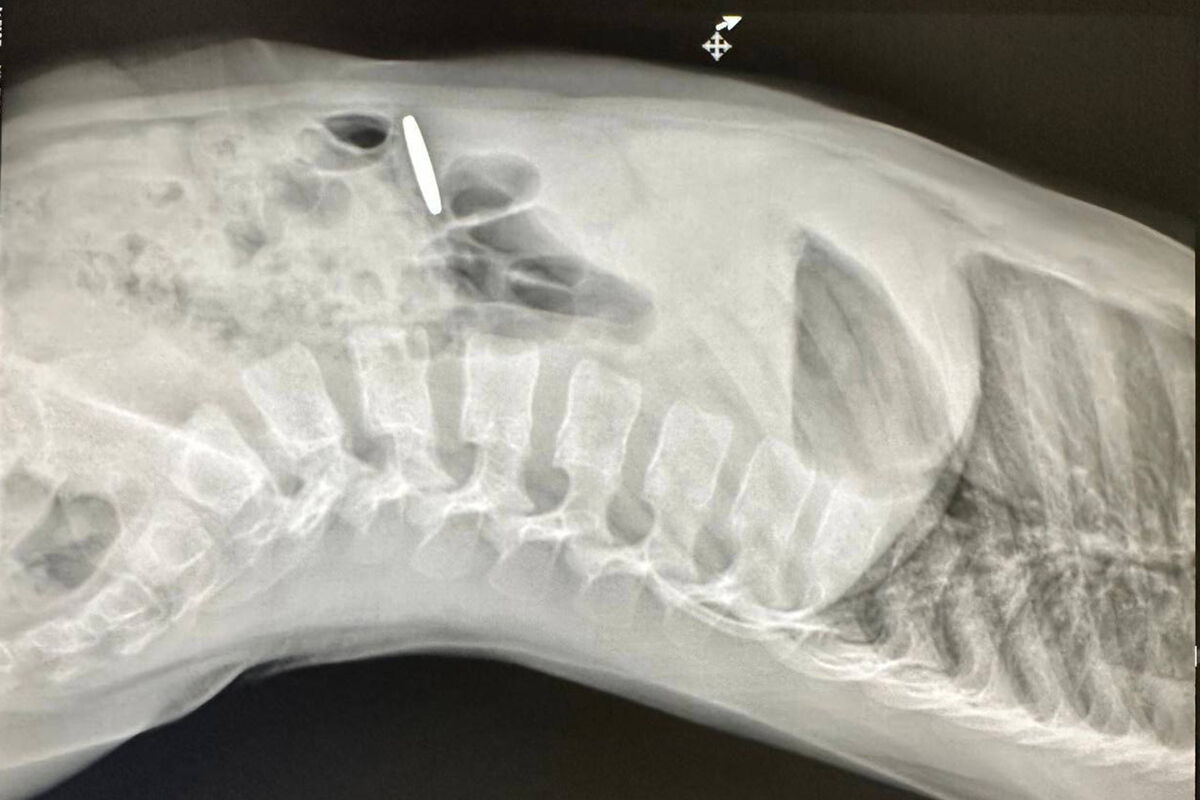

Родители маленького мальчика обратились за помощью в медицинское учреждение, где по результатам рентгенографии у него выявили в пищеварительном тракте инородный предмет. Им оказалась монета.

Поскольку монета не продвигалась дальше, медики приняли решение провести эндоскопическое вмешательство. В ходе процедуры инородный объект был успешно извлечен.

Как выяснилось, юный пациент проглотил монету номиналом 10 киргизских сомов. После проведенной манипуляции состояние ребенка не вызывало опасений, и вскоре его выписали домой.